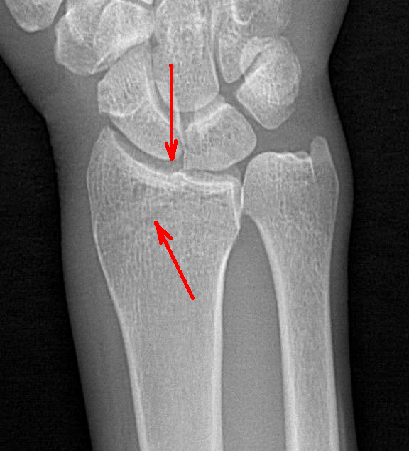

動態(tài)DR具備高清攝像和動態(tài)透視、實時高清點片等多種功能,對于隱匿性肋骨骨折的診斷優(yōu)勢明顯。